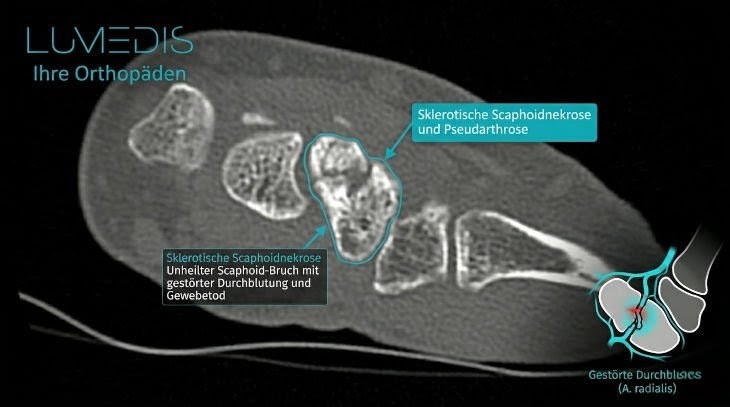

CT eines Morbus Preisers

MRT der Handwurzel mit einem beginnenden Morbus Preiser